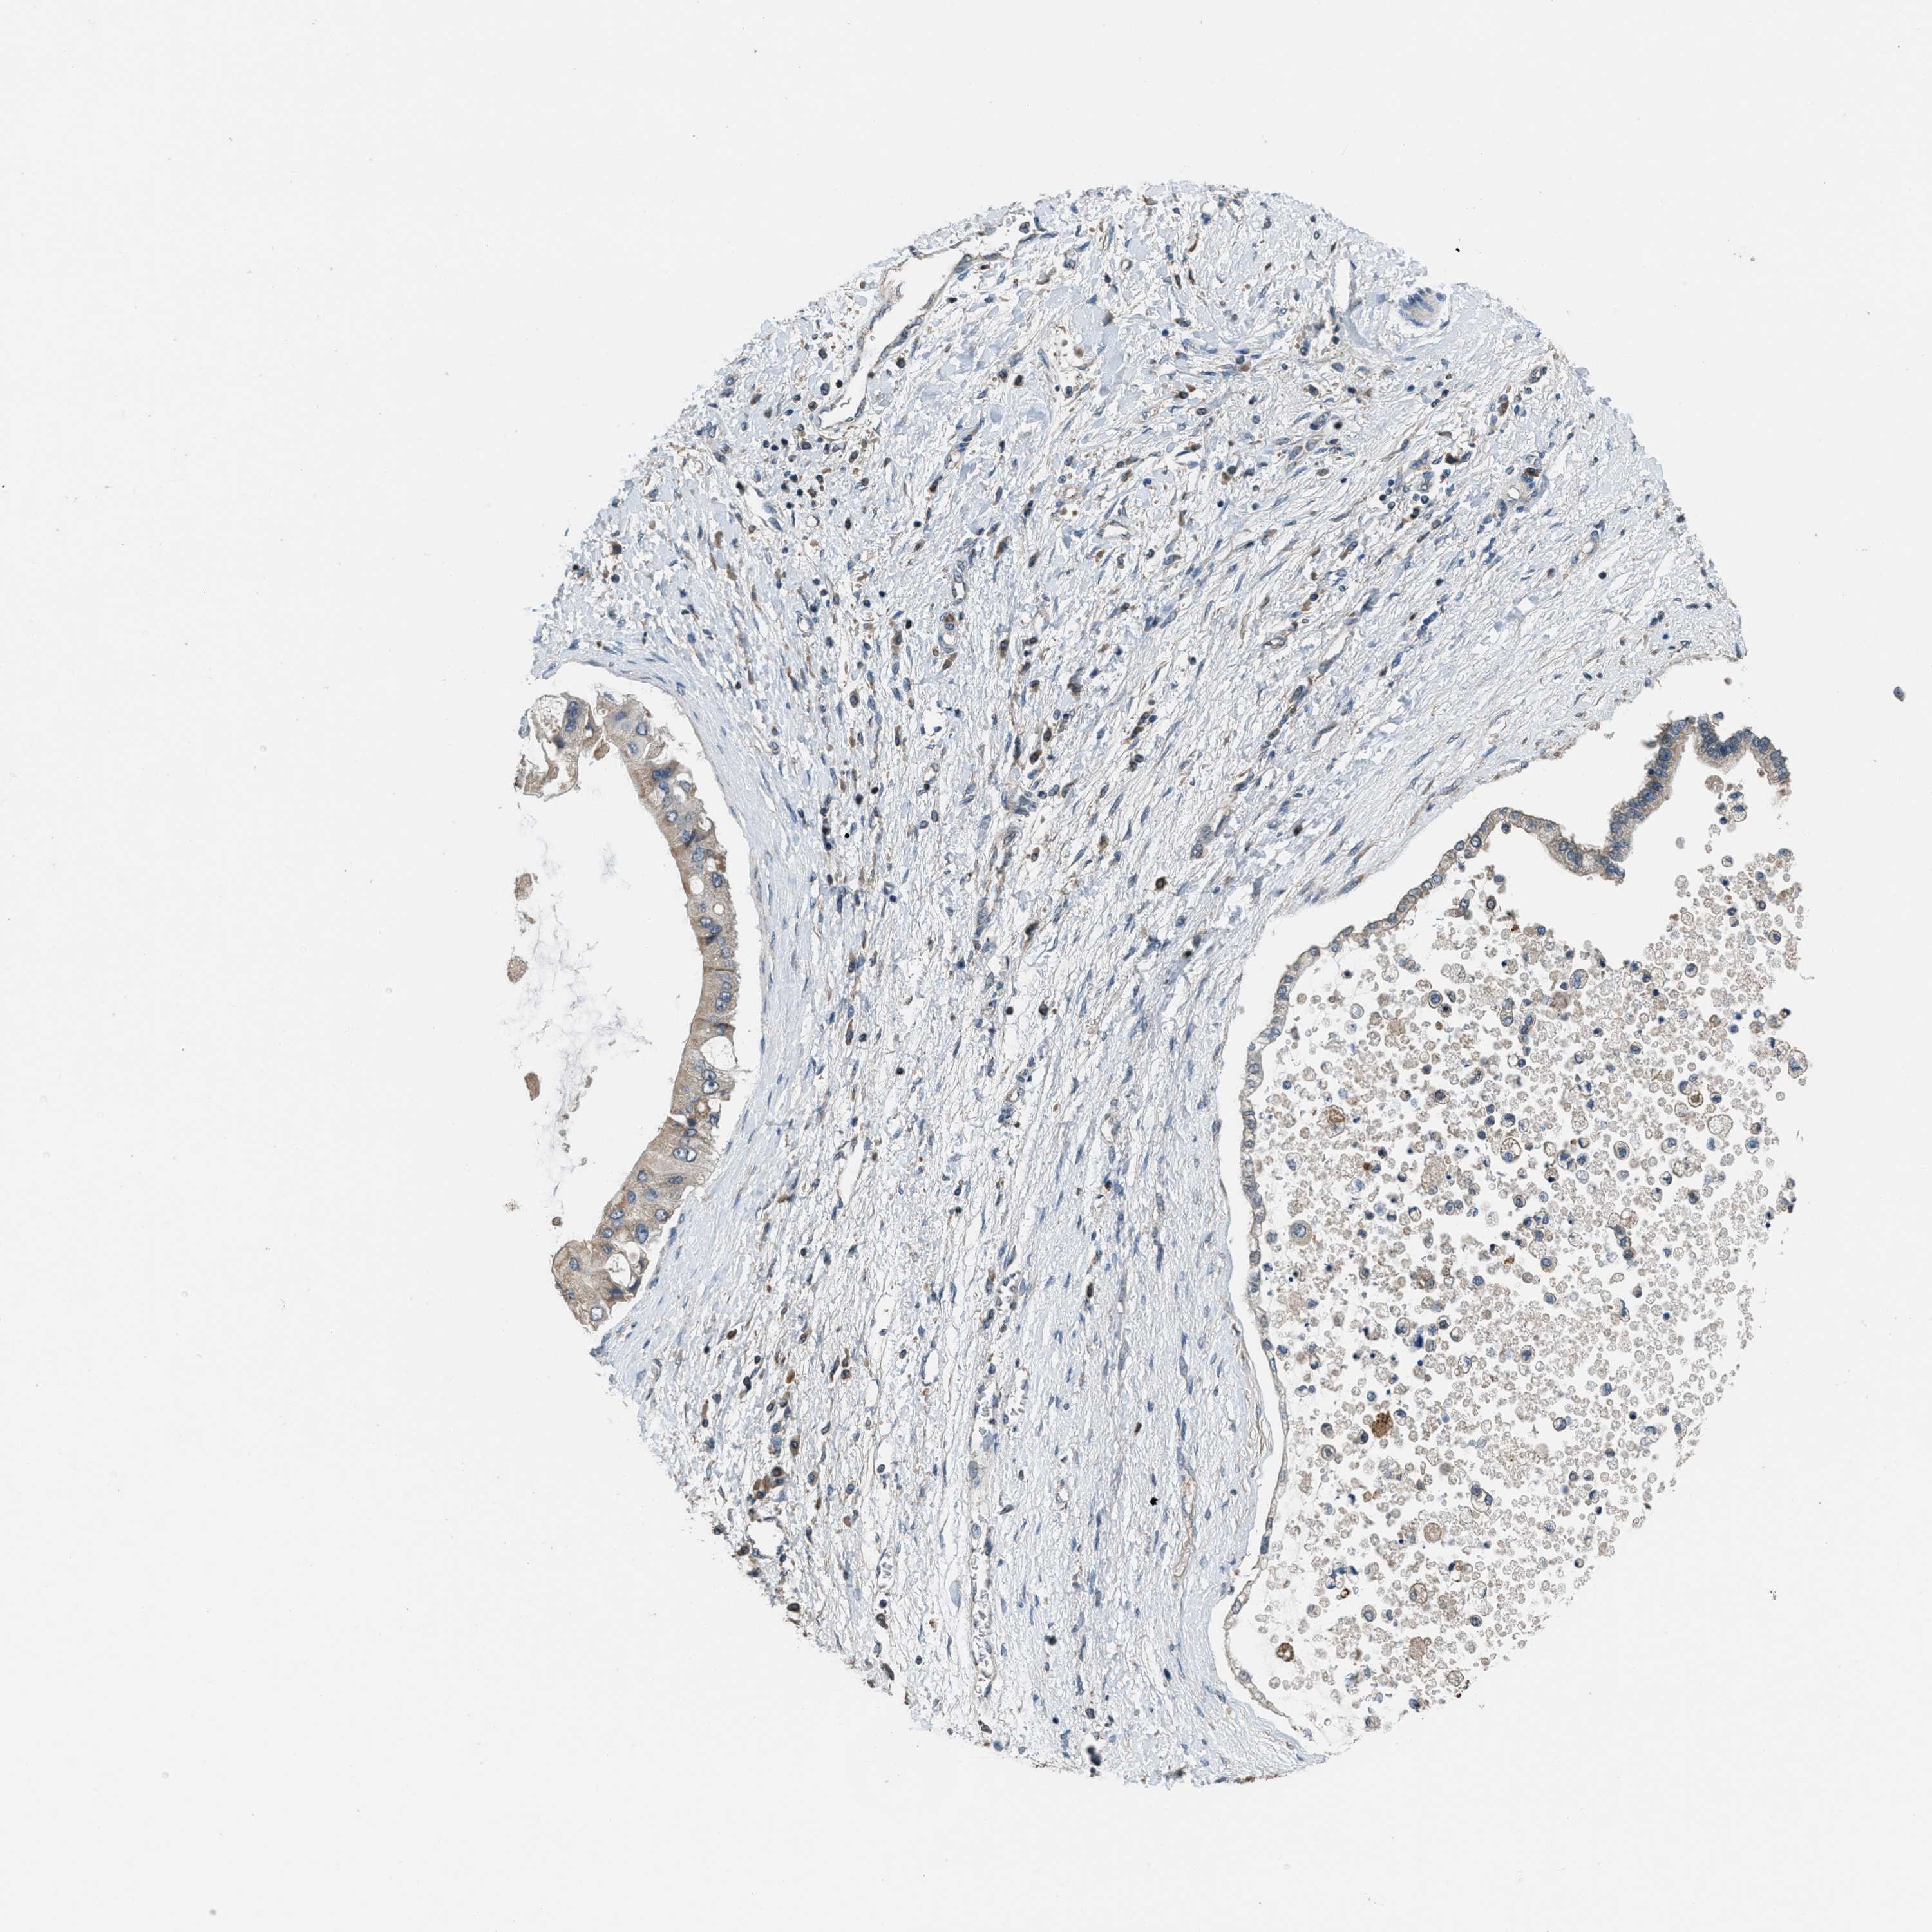

LIVER CANCER - Protein expressioni

A mouse-over function shows sample information and annotation data. Click on an image to view it in a full screen mode. Samples can be filtered based on level of antibody staining by selecting one or several of the following categories: high, medium, low and not detected. The assay and annotation is described here.

Antibody stainingi

Antibody staining in the annotated cell types in the current human tissue is reported as not detected, low, medium, or high, based on conventional immunohistochemistry profiling in selected tissues. This score is based on the combination of the staining intensity and fraction of stained cells.

Each image is clickable and will lead to virtual microscopy that enables deeper exploration of all samples and also displays staining intensity scores, fraction scores and subcellular localization as well as patient and tissue information for each sample.

Antibody HPA043704

Antibody CAB017782

Staining

High

Medium

Low

Not detected

Intensity

Strong

Moderate

Weak

Negative

Quantity

>75%

75%-25%

<25%

None

Location

Nuclear

Cytoplasmic/membranous

Cytoplasmic/membranous,nuclear

Cholangiocarcinoma

Carcinoma, Hepatocellular, NOS